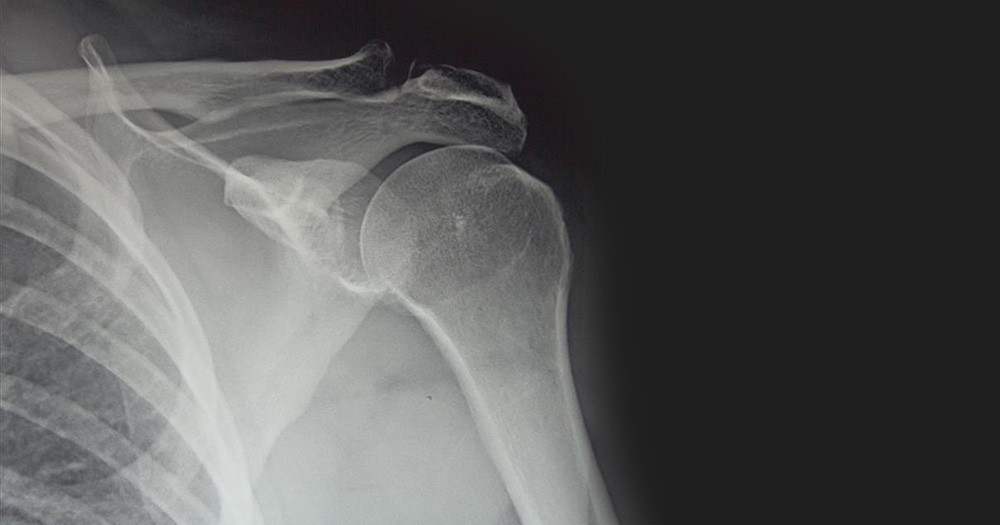

A hairline fracture is a tiny crack in a bone. Unlike stable fractures and compound fractures, a hairline fracture doesn’t go all the way through the bone, but that doesn’t mean it’s any less serious.

The bones of your feet and ankles are most at risk of developing hairline fracture, particularly if you participate in high-impact sports, such as running or gymnastics. However, fractures can develop on any bone, including the bones of your hands, arms, and shoulders.